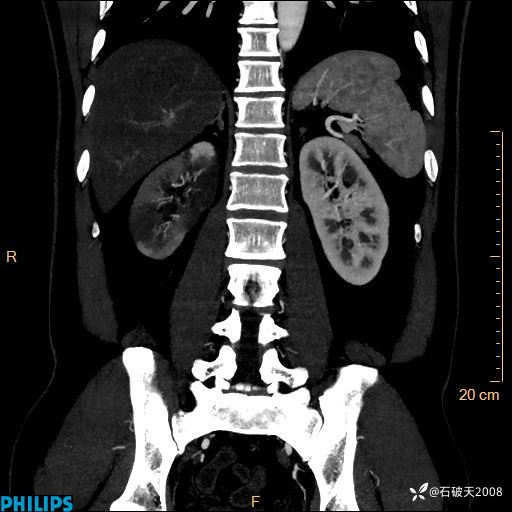

平扫轴位

冠状位